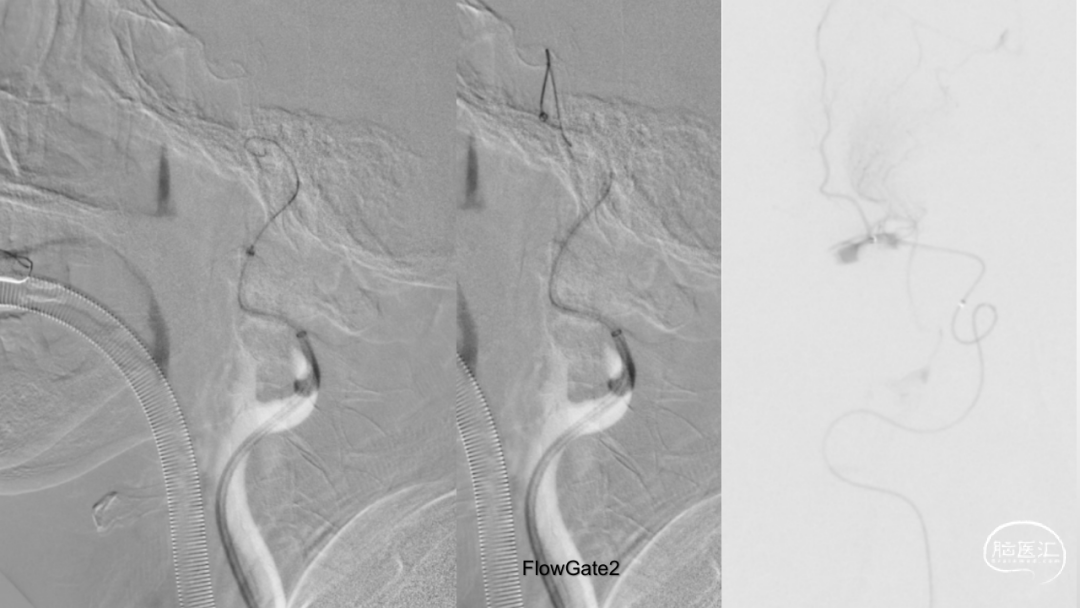

取之有道·第54期|李子付:Flowgate2取栓应用

看李子付解“取之有道”

滑动浏览更多内容